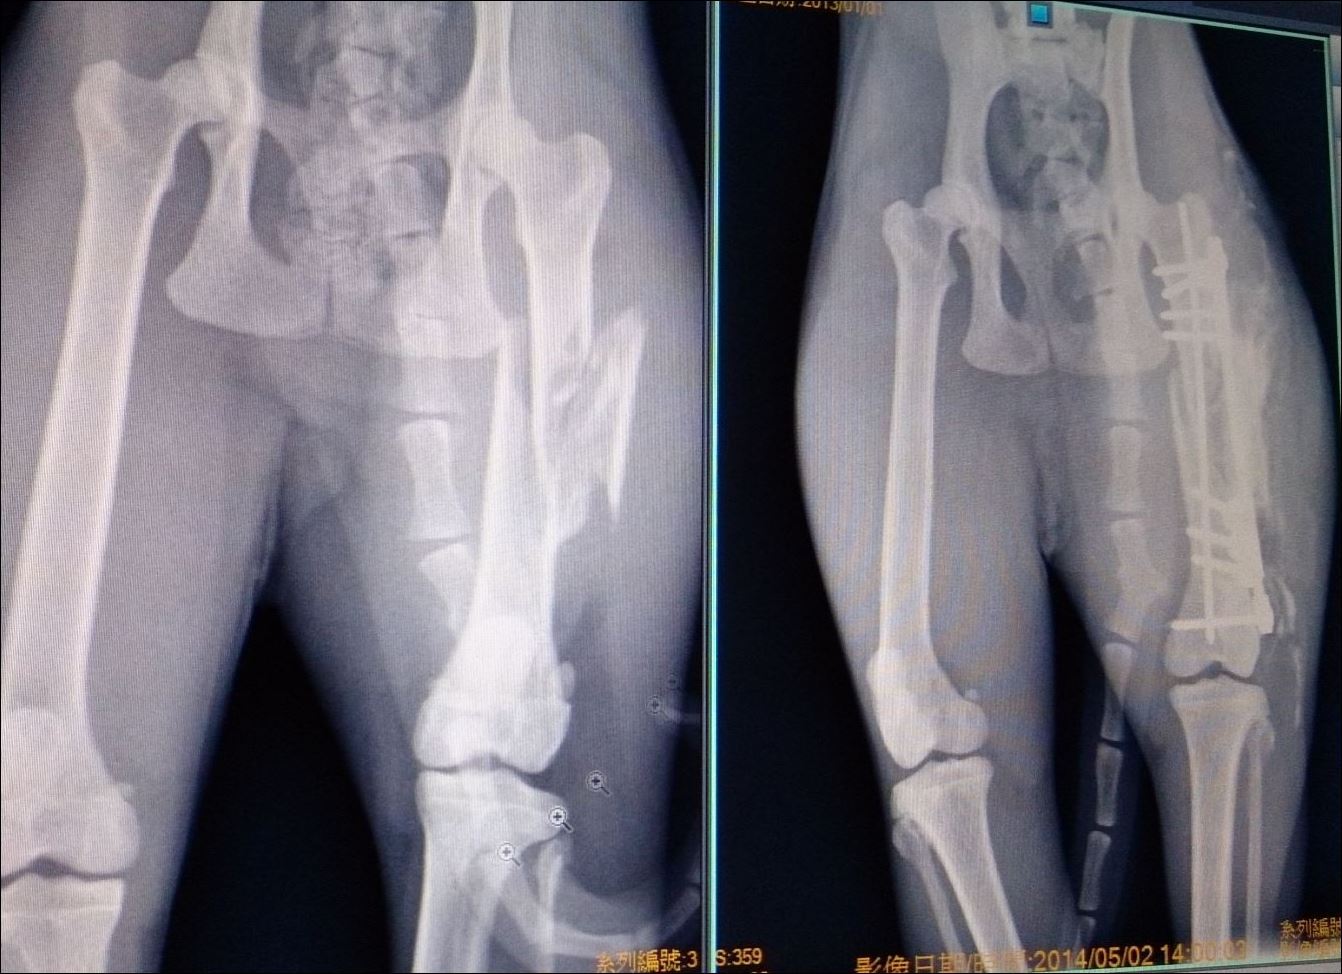

帶到急診醫院後發現是左大腿粉碎性骨折,

經過協會幫忙將貓咪帶往愛屋進行治療~醫生判斷是近期的傷口,要手術的話最好儘快實施,由於是粉碎性骨折手術較為複雜,但因為驗出貓瘟反應又有貧血症狀,必須隔離住院先觀察

玳瑁雖也有努力的吃飯但還需偶爾灌食,住院4日後經過點滴營養輸液,貧血狀況才有好轉,進行手術也順利完成,醫生劃刀後才曉得原來斷片有四片十分棘手,利用骨板與骨釘才能固定,但因為住院期間骨頭已有生長組織,手術進行變得更困難,醫生已儘量將錯位的關節與斷片拉回..所幸術後X光確認骨折後左腳和右腳的長度只有些微得差距不會影響貓咪行走跑跳

玳瑁拆線後,醫生認為術後的傷口復原狀況和骨頭位置良好,可以出院養傷,貓溫複驗也已經恢復為陰性~謝謝TNR協會及關心玳瑁的大家